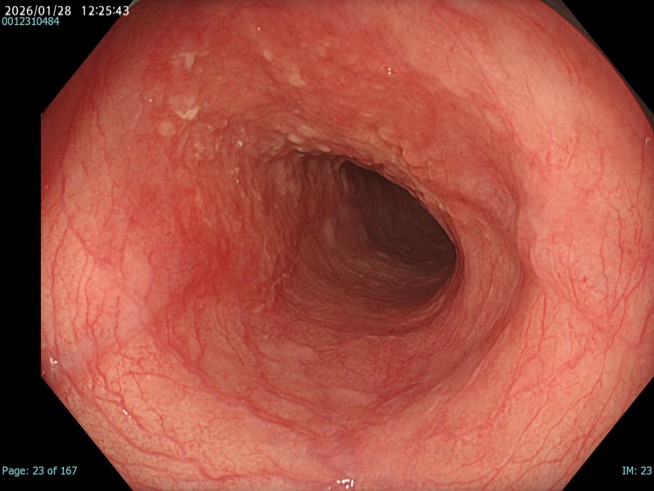

• NBI観察(中遠景)

強調設定:A8

図2

NBIにすることで白色光観察と比較して同部位の粘膜粗造が目立つ。一方で色調変化は軽度でDLも部分的には認識できるが、不明瞭な部分もあり、正確な領域評価が難しい。